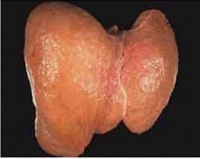

病理[编辑 | 编辑源代码]

正常人的肝内总脂肪量,约占肝重的5%,内含磷脂、甘油三酯、脂酸、胆固醇及胆固醇脂。脂肪量超过5%为轻度脂肪肝,超过10%为中度脂肪肝,超过25%

为重度脂肪肝。当肝内总脂肪量超过30%时,用B超才能检查出来,被B超检查确诊为“脂肪肝”。而脂肪肝患者,总脂量可达40%-50%,有些达60%以上,主要是甘油三酯及脂酸,而磷脂、胆固醇及胆固醇脂只少量增加。脂肪肝治愈的关键在于早发现、早治疗。

脂肪肝是一种多病因引起的脂肪大肝细胞内异常积累的病理状态。这种病理状态是肝脏对各种损伤产生的最常见反应。